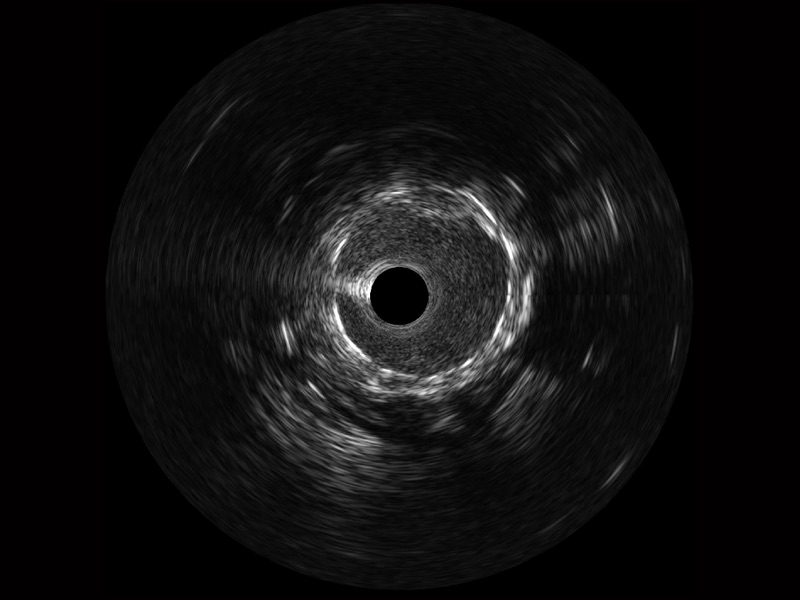

• 传统IVUS图像

对比传统IVUS导管成像,不朽情缘宽频IVUS图像的近场支架梁显影更细腻,远场中膜外血管仍清晰可辨,兼顾远中近,兼顾分辨力与穿透深度